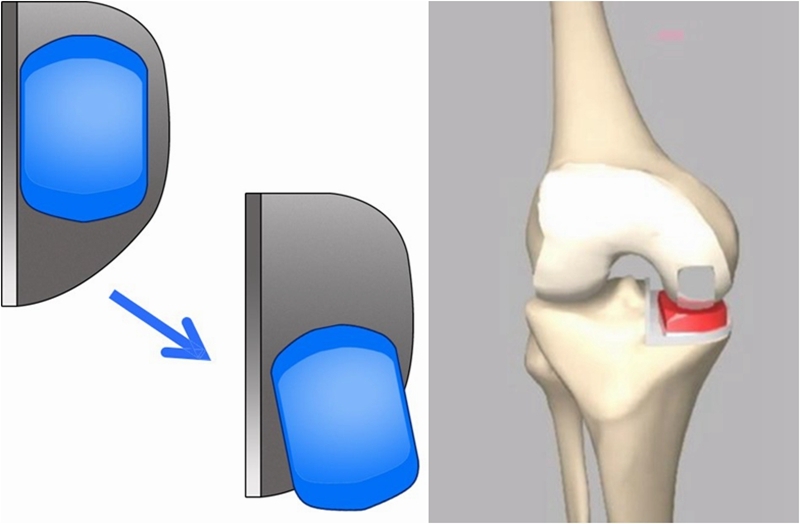

OUKA原理:充分填充,恢复自然。

伸直位外翻应力下内侧间隙打开

屈曲90°位外翻应力下内侧间隙打开

手术技术示意图

垫片移动轨迹测量